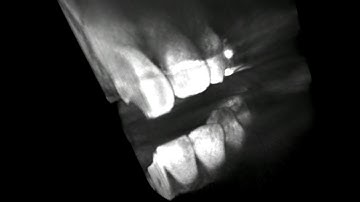

DICOM Visualization